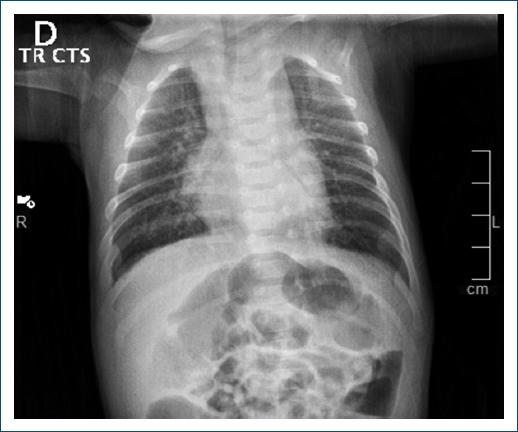

La radiografía mostró mesocardia con levoápex, con hipertensión venocapilar (Fig. 1). Se realizaron ecocardiograma transtorácico y cateterismo cardíaco, los cuales concluyen situs solitus atrial y abdominal, mesocardia con dextroápex, retornos venosos sistémicos y pulmonares lateralizados, conexión atrioventricular de tipo discordante y modo imperforado por ausencia de conexión atrioventricular izquierda, atresia tricuspídea e inversión ventricular (topología de mano izquierda) con las siguientes características: defecto interatrial pequeño y restrictivo con gradiente medio de 10 mmHg (Fig. 2); conexión ventriculoarterial tipo doble vía de salida del ventrículo derecho (rudimentario) modo perforado con aorta anterior e izquierda y doble infundíbulo, válvula pulmonar bivalva y displásica sin estenosis pulmonar; comunicación interventricular de entrada con extensión a la salida no obstructiva (Fig. 3), conducto arterioso persistente, disfunción diastólica del ventrículo sistémico y función sistólica conservada.

Figura 1 Radiografía de tórax antero posterior, observando situs solitus abdominal y pulmonar, mesocardia con levoápex, sin cardiomegalia, sin crecimiento de cavidades, arco aórtico a la izquierda, flujo pulmonar disminuido con hipertensión venocapilar.